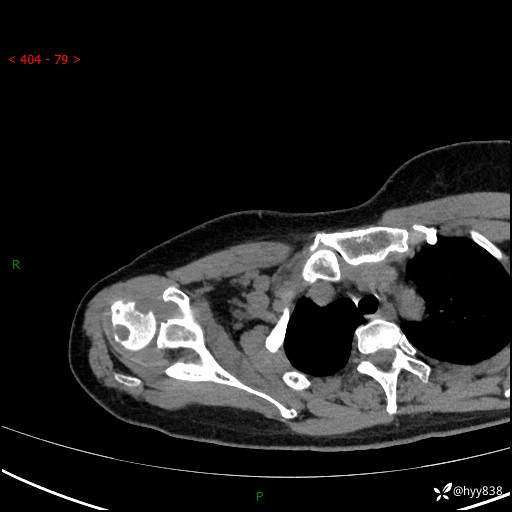

右肩关节CT平扫